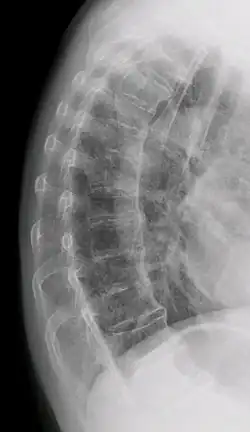

Confluent ossification of multiple contiguous vertebral bodies in diffuse idiopathic skeletal hyperostosis (DISH) -